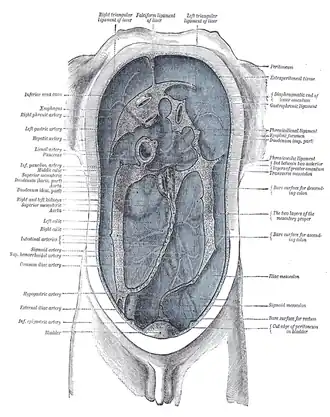

Topography of thoracic and abdominal viscera

Topography of thoracic and abdominal viscera -